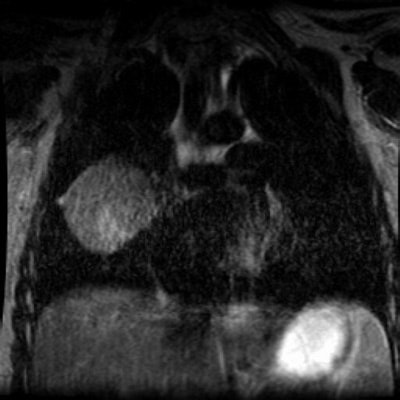

T2 weighted MR images demonstrate a region of increased signal intensity within the mass suggesting necrosis: